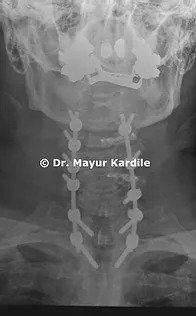

X-ray of the cervical spine revealed kyphotic alignment of the cervical spine

The patient was operated with C3 to C7 Laminoplasty with Posterior instrumented fusion from C3 to T2.

The goal of this procedure was to decompress the spinal cord and restore the normal lordotic alignment of the cervical spine